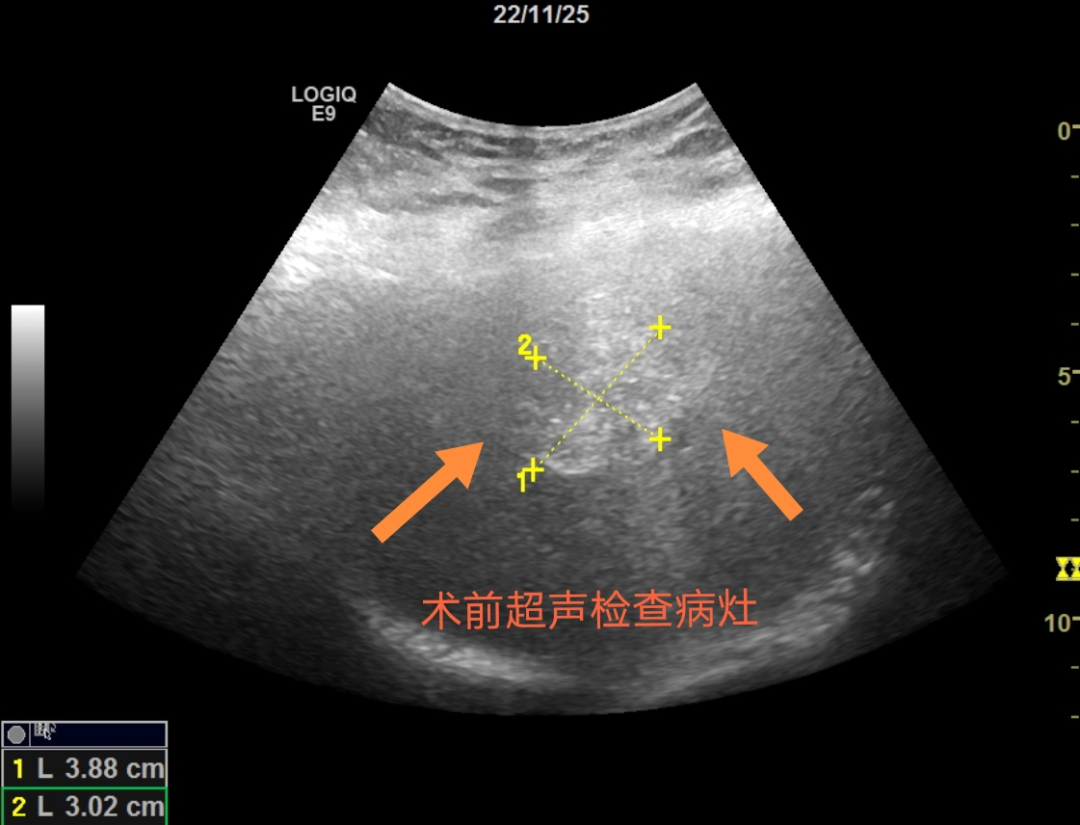

前不久,P女士在结肠癌术后进行腹部超声复查时发现肝脏上有三个低回声结节,再通过增强CT检查后医生结合病史考虑为肝脏转移灶。这样的结果,对P女士来说无疑为雪上加霜,想到自己去年才进行过一项大手术,难道还要再手术一次吗?对此,P女士及其家人感到迷茫。

察觉到P女士的顾虑以及她不想再进行二次手术的意愿后,消化内科的管床医生多次与任宏义谈论病情,在请教罗鸿昌教授仔细评估后认为可以采用超声引导下微波消融技术治疗患者的肝脏转移灶,而且术后恢复快,疗效好。这对于P女士及家属来说无疑是最好的消息。任宏义向患者及家属详细介绍了微波消融的方法、风险、注意事项及并发症等,罗鸿昌教授和任宏义对P女士的病情进行了术前讨论及严谨的手术设计